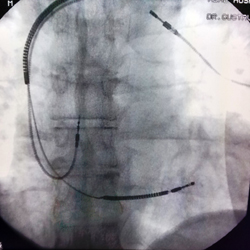

Portador de marcapasso há oito anos, Jorge Cubits precisou recorrer ao cardiologista quando foi diagnosticado com um tumor na cabeça. “Recentemente, apareceu um tumor no meu cérebro e eu tinha que fazer o exame de ressonância magnética com urgência, mas não podia realizá-lo com os eletrodos de marcapasso que já estavam implantados. Era necessário trocar por outros compatíveis”, pontua Jorge. Além do exame, o médico deve ser submetido a uma radiocirurgia estereotáxica: “Nesse tipo de procedimento, canhões emitem radiações que desintegram o tumor. Para isso, entretanto, é preciso fazer uma ressonância nuclear magnética, que é contra-indicada nesses pacientes por apresentar um risco potencial de induzir diversas complicações, inclusive com risco de vida, para os portadores de dispositivos cardíacos implantáveis não compatíveis com esse exame”, avalia Gustavo. Para realizar a troca de eletrodos, o cardiologista utiliza um fio guia de suporte por dentro do eletrodo e uma bainha extratora de eletrodos de marcapasso. Com a tecnologia de última geração, o especialista consegue remover os cabos com maior tranquilidade e segurança. “É importante extrair eletrodos que estejam com problema ou apresentam alguma possível complicação para a vida do paciente, como no caso de Jorge. O habitual é desligar os cabos-eletrodos com problema, deixando-os dentro do coração do paciente e adicionar outros novos. Alguns pacientes têm quatro, cinco ou até mais eletrodos dentro do coração”, aponta. Em média, cada eletrodo demanda uma hora para ser removido.